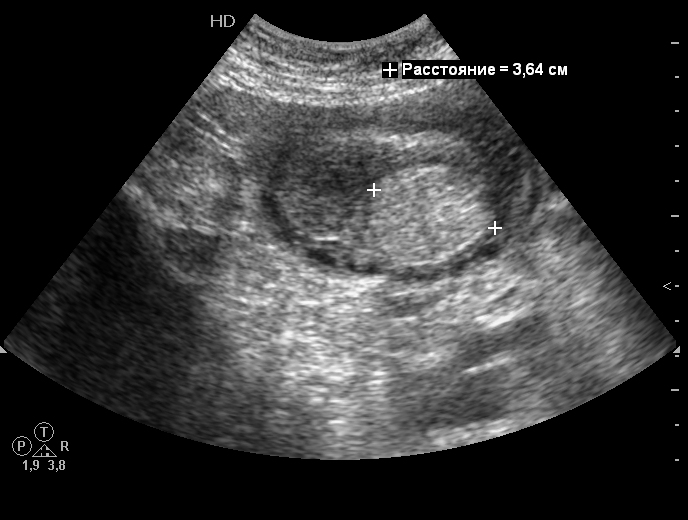

Опухоль и инвагинация тонкой кишки - УЗИ

А вот причина

Serg писал(а):что это? :cry:

Да, присоединяюсь, - что это?

яичник закрутился?

каловый завал :geek:

Непроходимость тонкокишечная?

да..ну тогда непрожованный кусок мяса или зубной протез...

Кусок мяса даже такой формы наверняка бы был переварен выше.

На протез не похоже по форме.